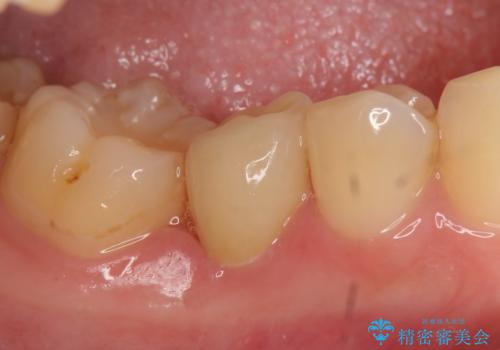

- 右下の歯に違和感があるといらっしゃった方の症例です。

右下6のクラウン及びメタルコアを除去したところ、歯根が垂直に破折していたため抜歯を提案し、ブリッジによる治療を行いました。

それに伴いクリアランス(補綴のための上下のスペース)の少ない右下臼歯部に、十分な歯冠長を確保するため歯冠長延長術を行いました。